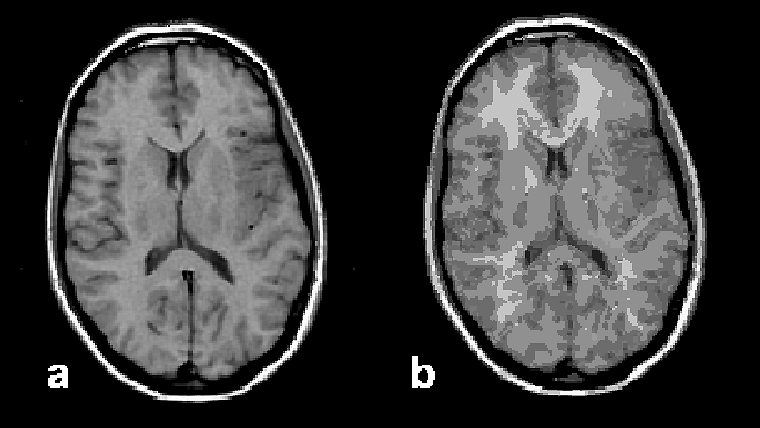

Figura 15-11:

Image segmentation: (a) original brain image, and (b) segmented image presenting 90 different tissue com­­po­nents.